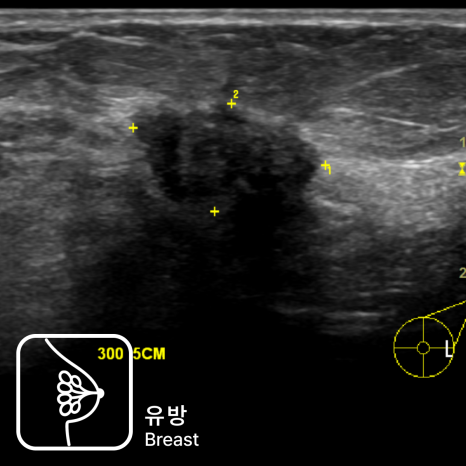

유방 초음파

유방 초음파는 초음파를 이용해 유방 조직 내부를 자세히 관찰하는 검사로, 만져지는 멍울이 물혹인지(낭종), 단단한 섬유선종인지, 염증이나 농양이 있는지, 또는 악성이 의심되는 종괴인지 평가하는 데 중요한 역할을 합니다. 특히…